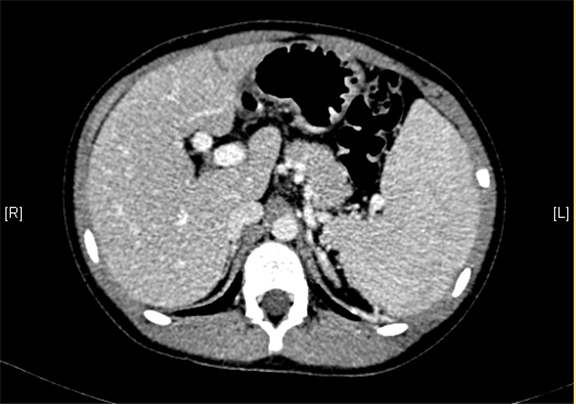

上腹部增强CT:门静脉主干走行迂曲、分支紊乱,考虑门静脉畸形可能性大,不除外门静脉海绵状变性。

术前CT检查:

动脉期

静脉期

平衡期